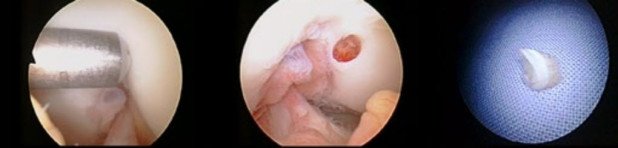

In diesem Fall bestätigte sich der Verdachtsbefund und es zeigte sich an der Patellagelenkfläche ein ausgedehnter und vollschichtiger Knorpelschaden (Abb. 2). In der gleichen Arthroskopie wurden Knorpelzellproben aus einer nicht belasteten Stelle des Gelenks entnommen (Abb. 3). Solche Proben werden jeweils zu einer Tissue-Engineering-Firma gesendet. Dort werden die Knorpelzellen in eine Zellkultur transferiert, um deren Zahl zu erhöhen.

Etwa drei bis vier Wochen nach der Entnahme können die Zellen wieder eingesetzt werden. Dies geschieht in einer zweiten, dann offenen Operation, bei der die eigenen Knorpelzellen, bereits auf einer dreidimensionalen Matrix besiedelt und passgenau auf die Defektgrösse zugeschnitten, eingesetzt und mit einem sehr feinen Faden am umliegenden Knorpel befestigt werden (Abb. 4). Nach Ablauf der Regenerationszeit konnte der Patient wieder schmerzfrei den Alltag bewältigen und im späteren Verlauf auch die volle sportliche Aktivität wieder aufnehmen. Es bestanden keine Beschwerden mehr im Bereich des rechten Kniegelenks. Das Kontroll-MRI ein Jahr nach der Operation zeigte eine wiederhergestellte Knorpeloberfläche mit guter Integration des Transplantates sowohl in den umliegenden Knorpel als auch in den unterliegenden Knochen. Dabei wies das Transplantat selbst eine dem umliegenden Knorpel vergleichbare Signalgebung auf – als Zeichen der physiologischen Regeneratqualität.